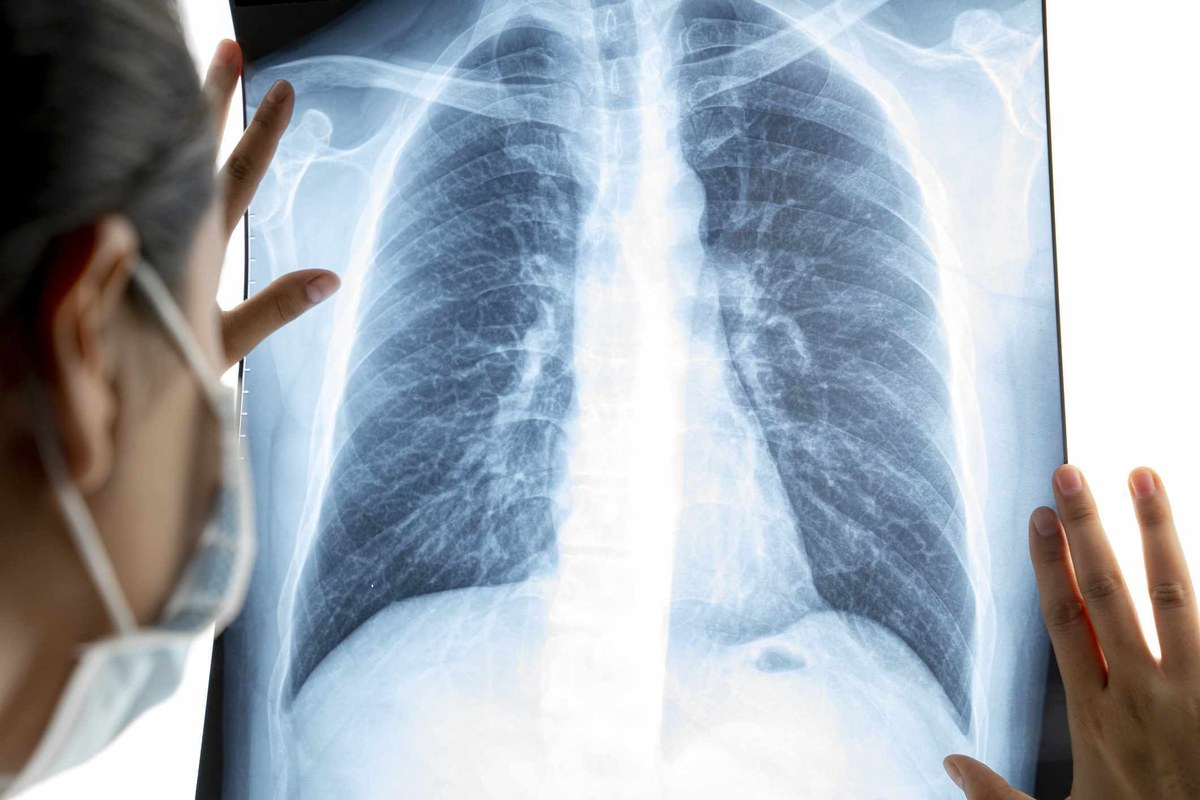

Key Bronchitis CXR Finding #3: Hyperinflated Lungs

Hyperinflated lungs are a key finding in bronchitis patients. This happens when airways get blocked, trapping air in the lungs. We’ll look at the signs of hyperinflation, why it happens in bronchitis, and the differences between acute and chronic cases.

Radiographic Signs of Hyperinflation

Hyperinflation means the lungs take up more space. On a chest X-ray, you can spot it by several signs. These include:

- Flattening of the diaphragm

- Increased retrosternal airspace

- Widening of the intercostal spaces

- A more horizontal orientation of the ribs

Mechanism in Bronchitis

In bronchitis, hyperinflation happens because airways get blocked. This blockage traps air, making the lungs overinflate. This effect is more common in chronic obstructive pulmonary disease (COPD), where bronchitis is a part.

Acute vs. Chronic Presentation

The look of hyperinflated lungs can vary between acute and chronic bronchitis. In acute bronchitis, the lungs might not be as overinflated and could get better. But in chronic bronchitis, the lungs stay overinflated for a long time because of ongoing blockage.